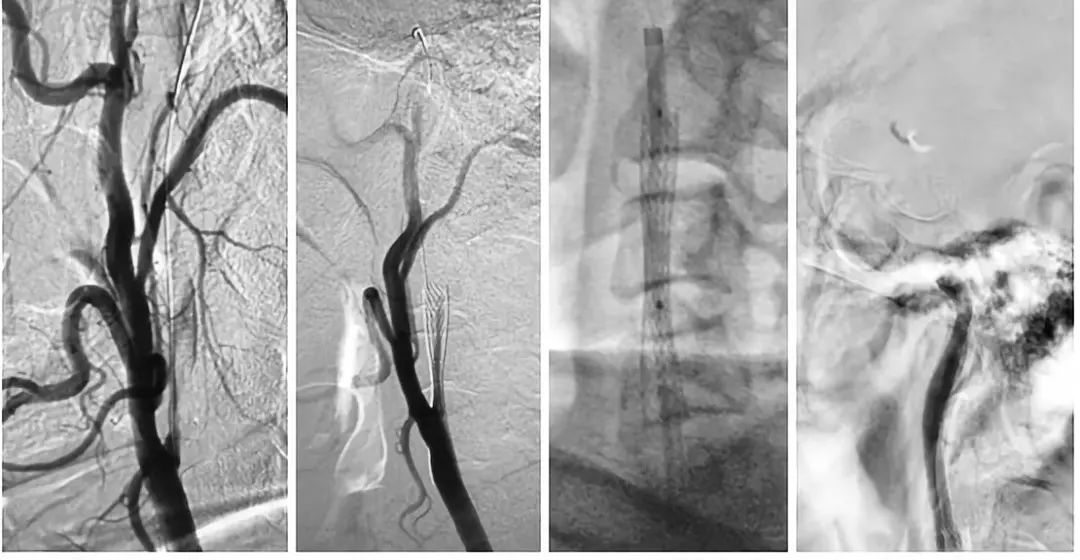

DSA结果提示:左侧颈内动脉次全闭塞,远端未见显影,左侧大脑中动脉闭塞,前交通动脉开放,左侧椎动脉起始部重度狭窄(图3-5)。

图3

图4

图5

局麻下,将8F导引导管上行至颈总动脉远端,在路径途指导下,将微导丝(Transcend)、微导管(Echelon-10)通过颈内动脉狭窄段至C2段,造影证实微导管位于真腔内,颈内动脉末端闭塞,交换出微导管,沿导丝送入Maverick(2.0x20mm)球囊至狭窄处,予以扩张球囊,造影提示狭窄有所改善,导引导管上行困难,遂沿导丝送入Wallstent(9x30mm)支架至狭窄处,释放支架,造影提示残余狭窄率约为60%,遂沿导丝送入LitePAC (4.0x30mm)球囊至狭窄处予以后扩张,造影提示狭窄明显改善,将球囊半充盈态势,导引导管沿球囊越过支架支颈内动脉C1段远端,再次造影示颈内动脉末端仍然闭塞,(图6)

图6